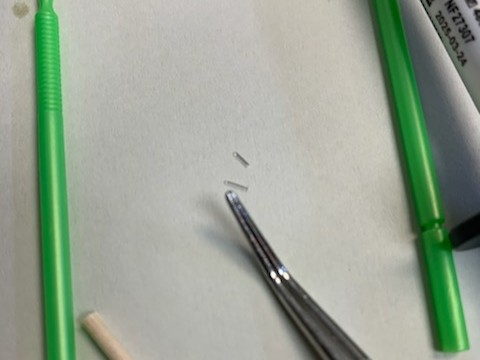

DentXpinTM – placed April, 12, 2012 and still holding strong.

1